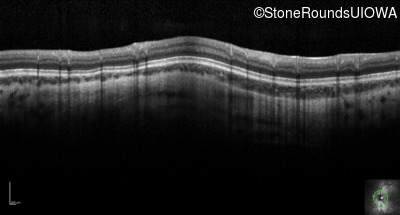

Optical Coherence Tomography - Right - 20/160 +1

Exemplar / OCT Stack

OCT Stack